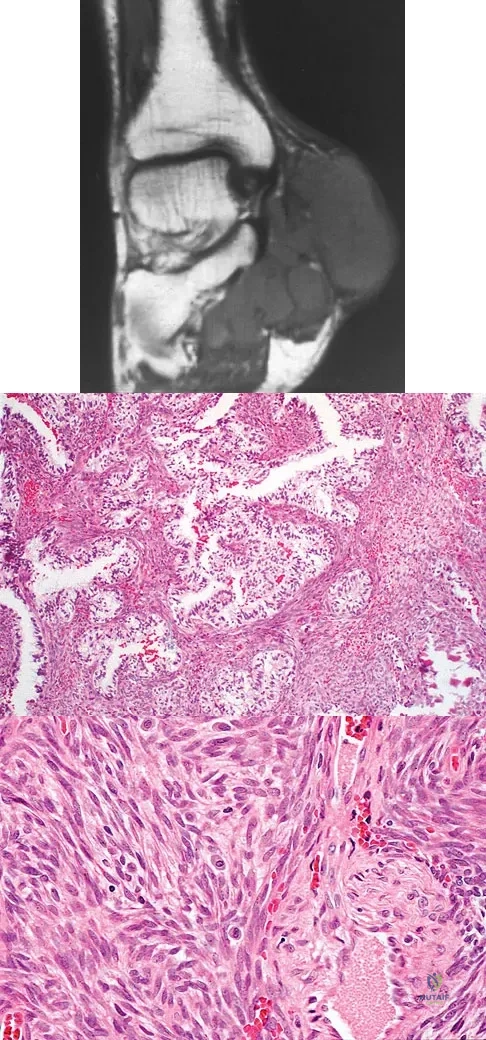

Question 63

A 40-year-old man has a painless mass around his left ankle. He notes minimal growth over the past year. An MRI scan is shown in Figure 73a, and biopsy specimens are shown in Figures 73b and 73c. What is the most likely diagnosis?

Explanation